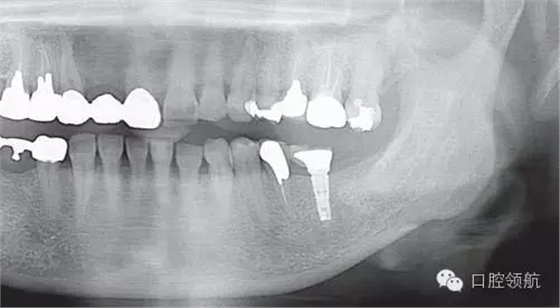

全景X線片上沒發(fā)現(xiàn)有骨吸收現(xiàn)象(圖2),發(fā)現(xiàn)在MGJ附近和種植體周圍齦溝里有白色顆粒的存在(圖3)。

圖2 當(dāng)日的全景X線片上沒發(fā)現(xiàn)有骨吸收現(xiàn)象。